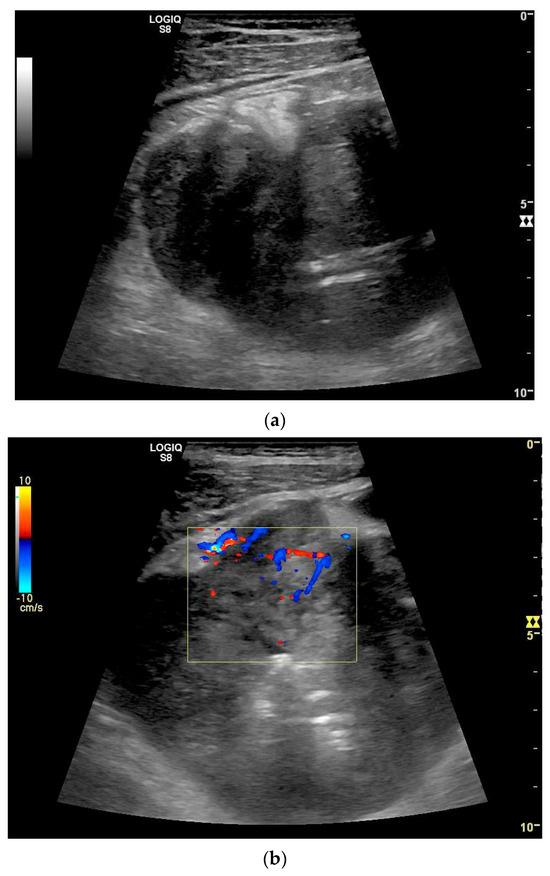

Figure 9.

Burkitt-Lymphoma. In a patient with weight loss, increased abdominal circumference, anemia, and physical weakness, the initial sonographic examination reveals an extensive tumor with intense hypoechogenicity and a connection to the jejunum in the left mid-abdomen. Despite its pronounced hypoechogenicity, a feeding vessel on CDI indicates a solid character (a). The tumor significantly thickens the wall and is intensely hypoechoic. The arrows point to the multisegmental hypoechoic wall thickenings (b). Normal wall structures are still visible (W), and the tumor extends beyond the wall (arrow) (c). In addition to delicate Kerckring folds (KF), there are significantly polypoid thickened KF with pronounced hypoechogenicity (d). The thickening of KF is very extensive (e). Wall thickening was found also in the stomach and colon and allowed endoscopic biopsy to establish the diagnosis.